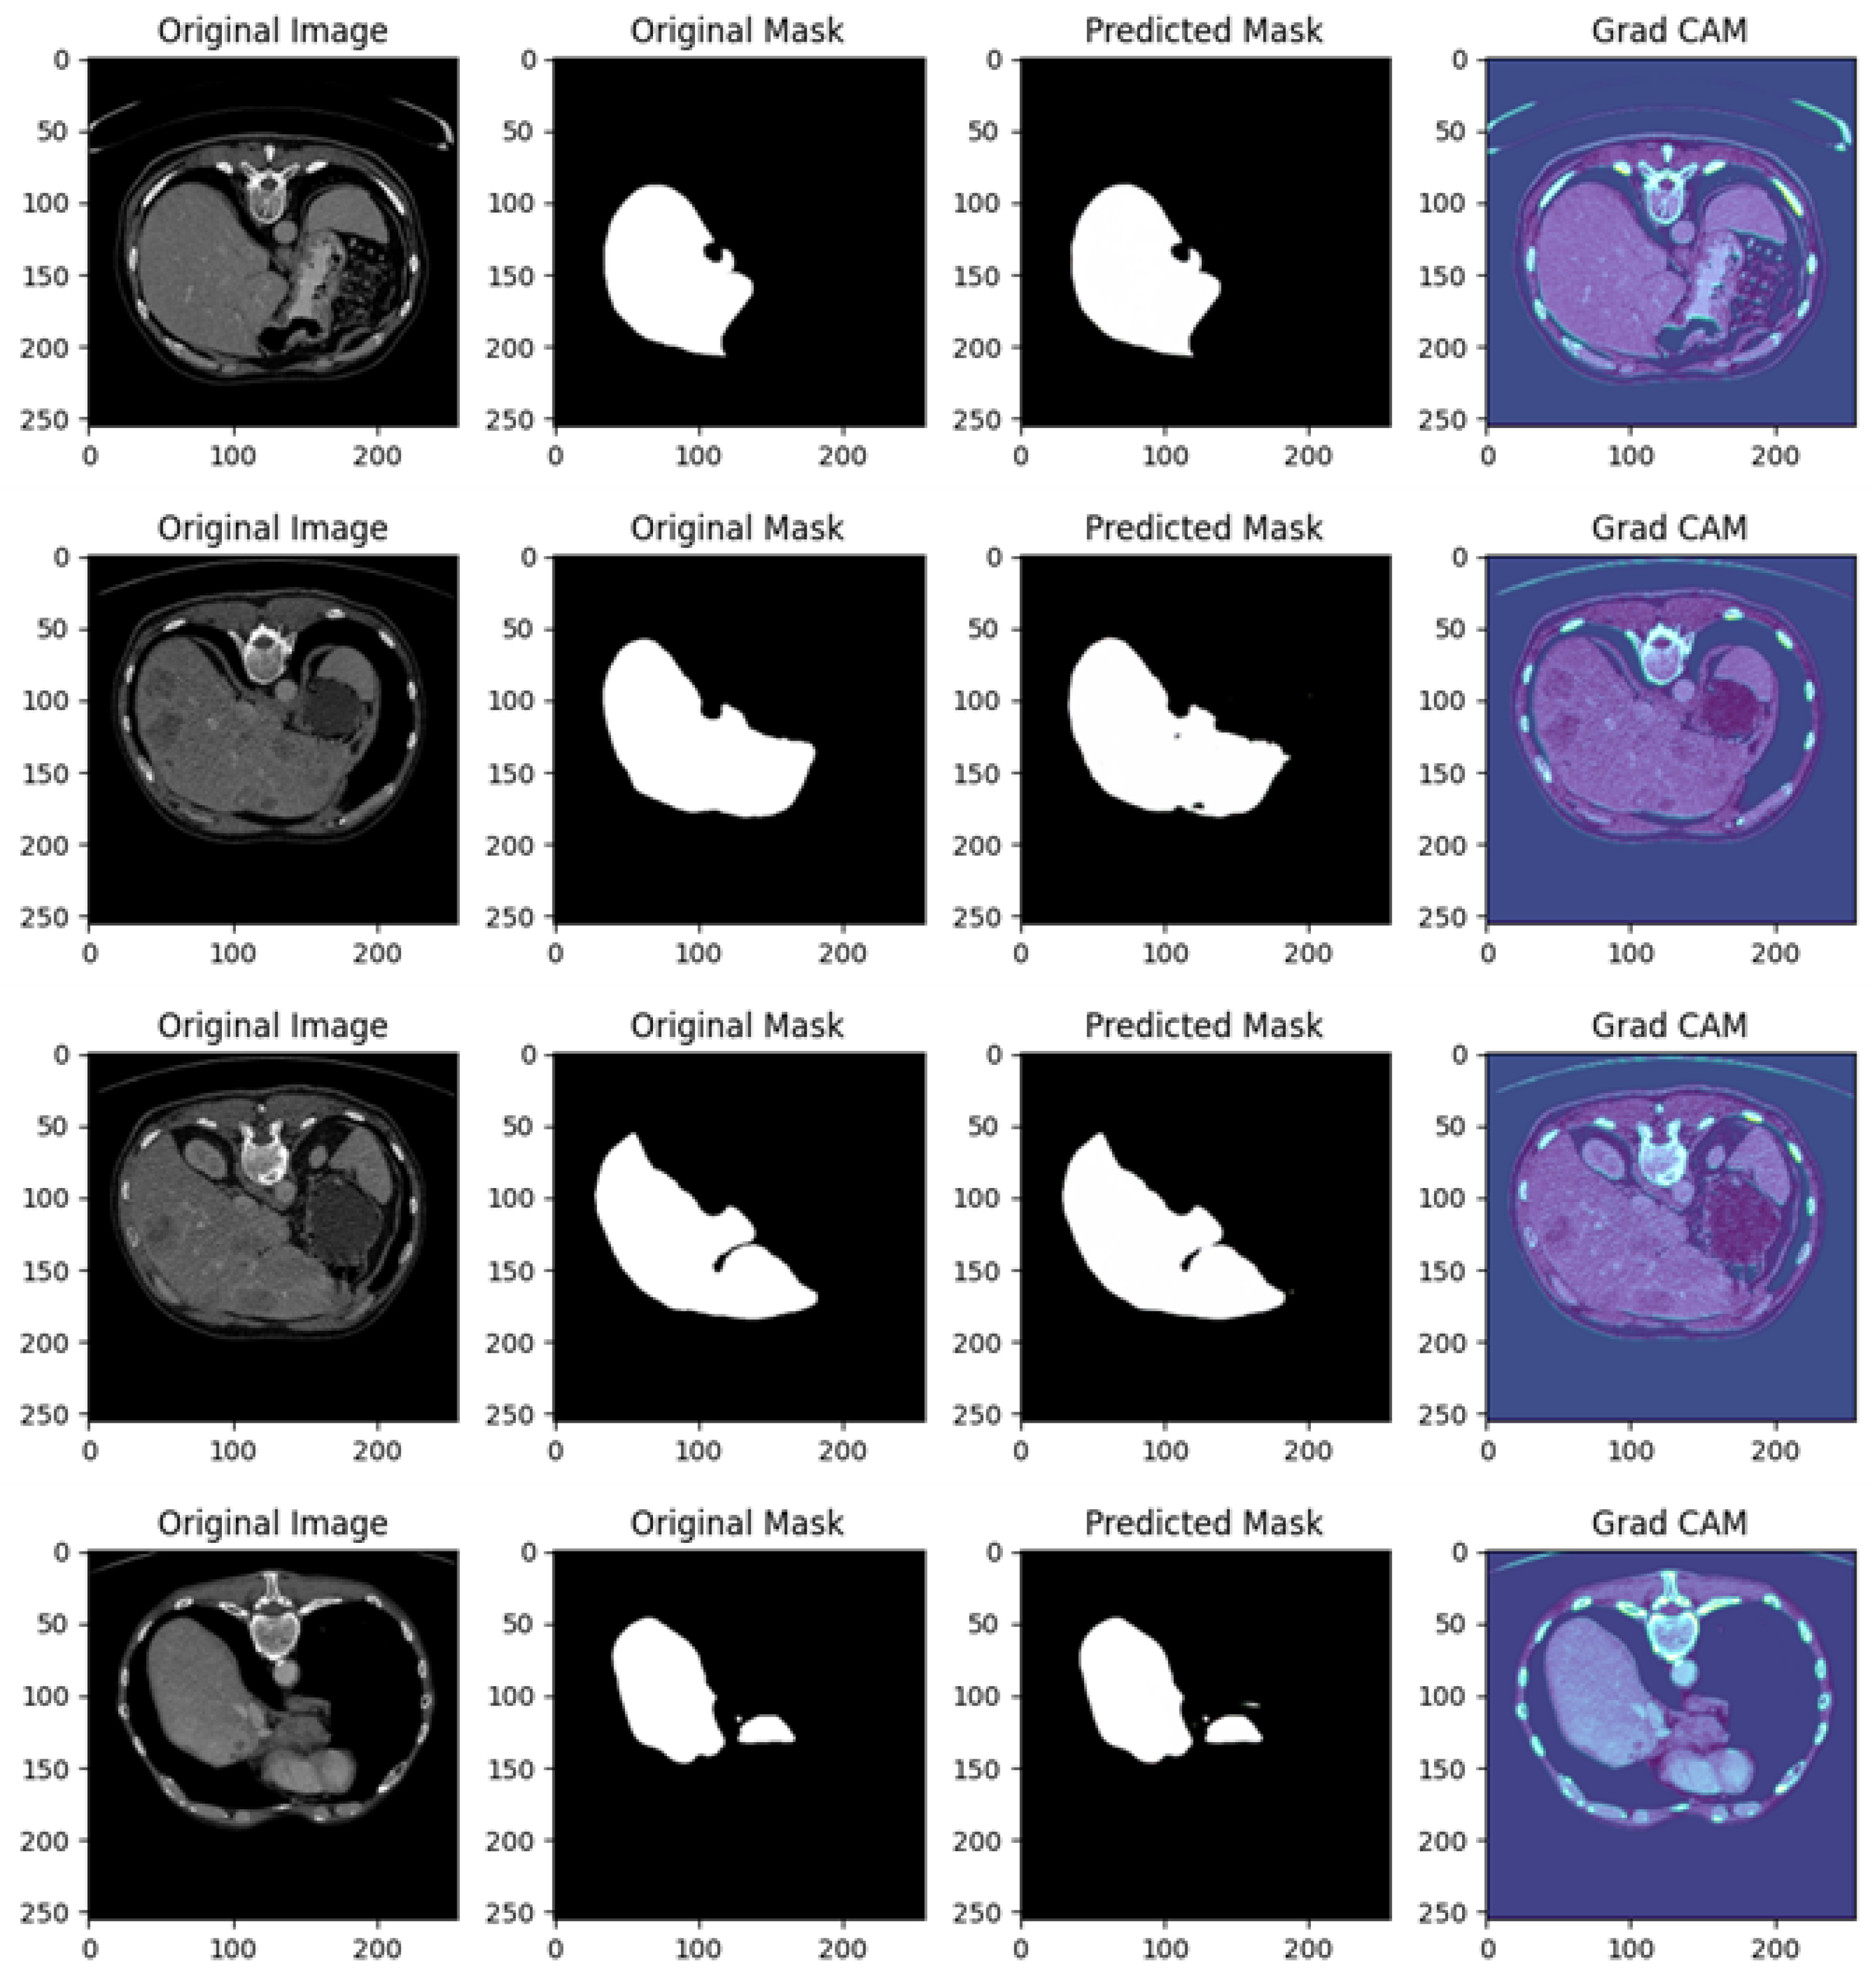

4.7. Experiment III Results

In this section, we provide the experimental analysis results related to Experiment III. The testing accuracy in this experiment is equal to 0.8948, with a Dice coefficient equal to 0.888 and an IoU metric with a value of 0.80.

Figure 10 shows several examples of prediction related to Experiment III.

Figure 10 is related to a comprehensive analysis of the segmentation predictions of a U-Net model across four different cases, each including the original image, original mask, predicted mask, and a Grad-CAM visualization.

Example of Prediction 1: The CT scan shows a cross-sectional view of the liver region, with surrounding anatomy clearly visible. In the original mask, the target organ (the liver) is accurately segmented. The U-Net model’s prediction closely follows the shape of the original mask, but there is a small under-segmentation issue, particularly around the edges of the liver. While the shape and size are mostly consistent, some fine details are missing. The Grad-CAM heatmap reveals that the model predominantly focuses on the liver region. However, there are some peripheral areas of activation outside the liver, which may explain the minor segmentation inaccuracies.

Example of Prediction 2: Another CT scan provides a slightly different perspective of the abdomen. The original mask segments the target organ over a larger area compared to the first row. The U-Net model’s prediction is very close to the original mask, capturing almost the entire organ accurately. Though there is a slight discrepancy in the boundary, the prediction is overall more accurate than the first one. The Grad-CAM heatmap shows that the model’s attention is well concentrated on the target organ, with minimal distractions outside the region of interest. This focused attention explains the good quality of the prediction.

Example of Prediction 3: This CT scan shows another cross-sectional view of the abdomen, where the original mask highlights a larger organ with precise contours. The U-Net model’s prediction performs well, capturing most of the organ. However, there is minor over-segmentation, with the model including some extraneous areas that do not belong to the target organ. Despite this, the overall shape of the organ is well preserved. The Grad-CAM heatmap shows strong activations around the liver area, but there are also peripheral regions activated, which correlates with the over-segmentation observed in the prediction.

Example of Prediction 4: This scan presents a slightly altered view of the abdomen, similar to the previous rows. In the original mask, the liver is clearly outlined. The U-Net prediction shows under-segmentation, where the model fails to capture the entire organ, especially around the edges. The size of the predicted mask is notably smaller than the original mask. The Grad-CAM heatmap indicates that the model’s focus is somewhat diffused, with significant attention placed on regions outside the target organ, which likely explains the under-segmentation seen in the predicted mask.

The U-Net model performs well overall, but the predictions show some variability. Prediction examples 2 and 3 display better segmentation results, with only minor deviations in boundary precision, while prediction examples 1 and 4 exhibit under-segmentation issues, where parts of the organ are missed.

In prediction examples 1 and 4, there is under-segmentation, meaning the model fails to capture the full extent of the target organ. In prediction example 3, over-segmentation is observed, where parts outside the target area are mistakenly included.

The Grad-CAM visualizations provide valuable insights into the model’s decision-making process. Prediction examples 2 and 3 show that the model focuses well on the relevant regions, leading to more accurate predictions. However, in prediction examples 1 and 4, the Grad-CAM maps reveal that the model is focusing on regions beyond the target, resulting in less precise predictions.

The U-Net model exhibits promising segmentation performance across the images, particularly in prediction examples 2 and 3, where the predictions closely match the original masks. The Grad-CAM visualizations effectively highlight areas where the model’s attention is misdirected, offering useful guidance for model tuning and enhancement.